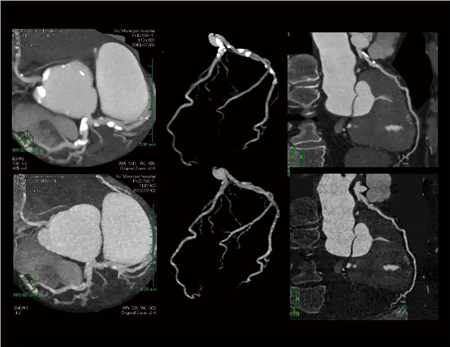

Dual Energy部門

及川徳章

(伊東市民病院医療技術部放射線室)

【背 景】右視床出血の既往のある70代,男性。早朝安静時に胸痛があり,紹介で当院受診。ECGで変化はなく,冠攣縮性狭心症を疑い心臓CT検査を施行。単純CTで石灰化を認め, HRも低心拍で安定していたため,Dual Energyによる撮影を行った。

【所 見】3Dワークステーション使用。PW MIP(左),MIP(中),前下行枝のMPR(右)。上段は時間分解能75ms MIX画像(カーネル:Ⅰ26f medium smooth)にて前下行枝および回旋枝に高度石灰化を認め,前下行枝♯6に高度石灰化を伴う有意狭窄が疑われた。しかし,下段のsyngo. Dual Energy Liver VNCを用いたIodine Imageでは,有意狭窄は認められなかった。

【ポイント】石灰化除去を行う場合,一般的にはsyngo. Body Bone Removalを使用するが,当院ではトライアル段階だがsyngo. Dual EnergyのLiver VNCを用いてDual Energyの処理設定を多少変更し,Iodine Imageを作成することで石灰化除去を行っている。石灰化によるブルーミングアーチファクト低減のため,再構成関数はSAFIREを用いたQ40f midiumを使用。これにより,石灰化除去後の内腔を良好に観察することができた。この方法はオペレータが異なっても再現性が良く,3Dワークステーションでの処理も簡単というメリットがある。被ばく線量はCARE Dose4D使用で10mSv程度だった。